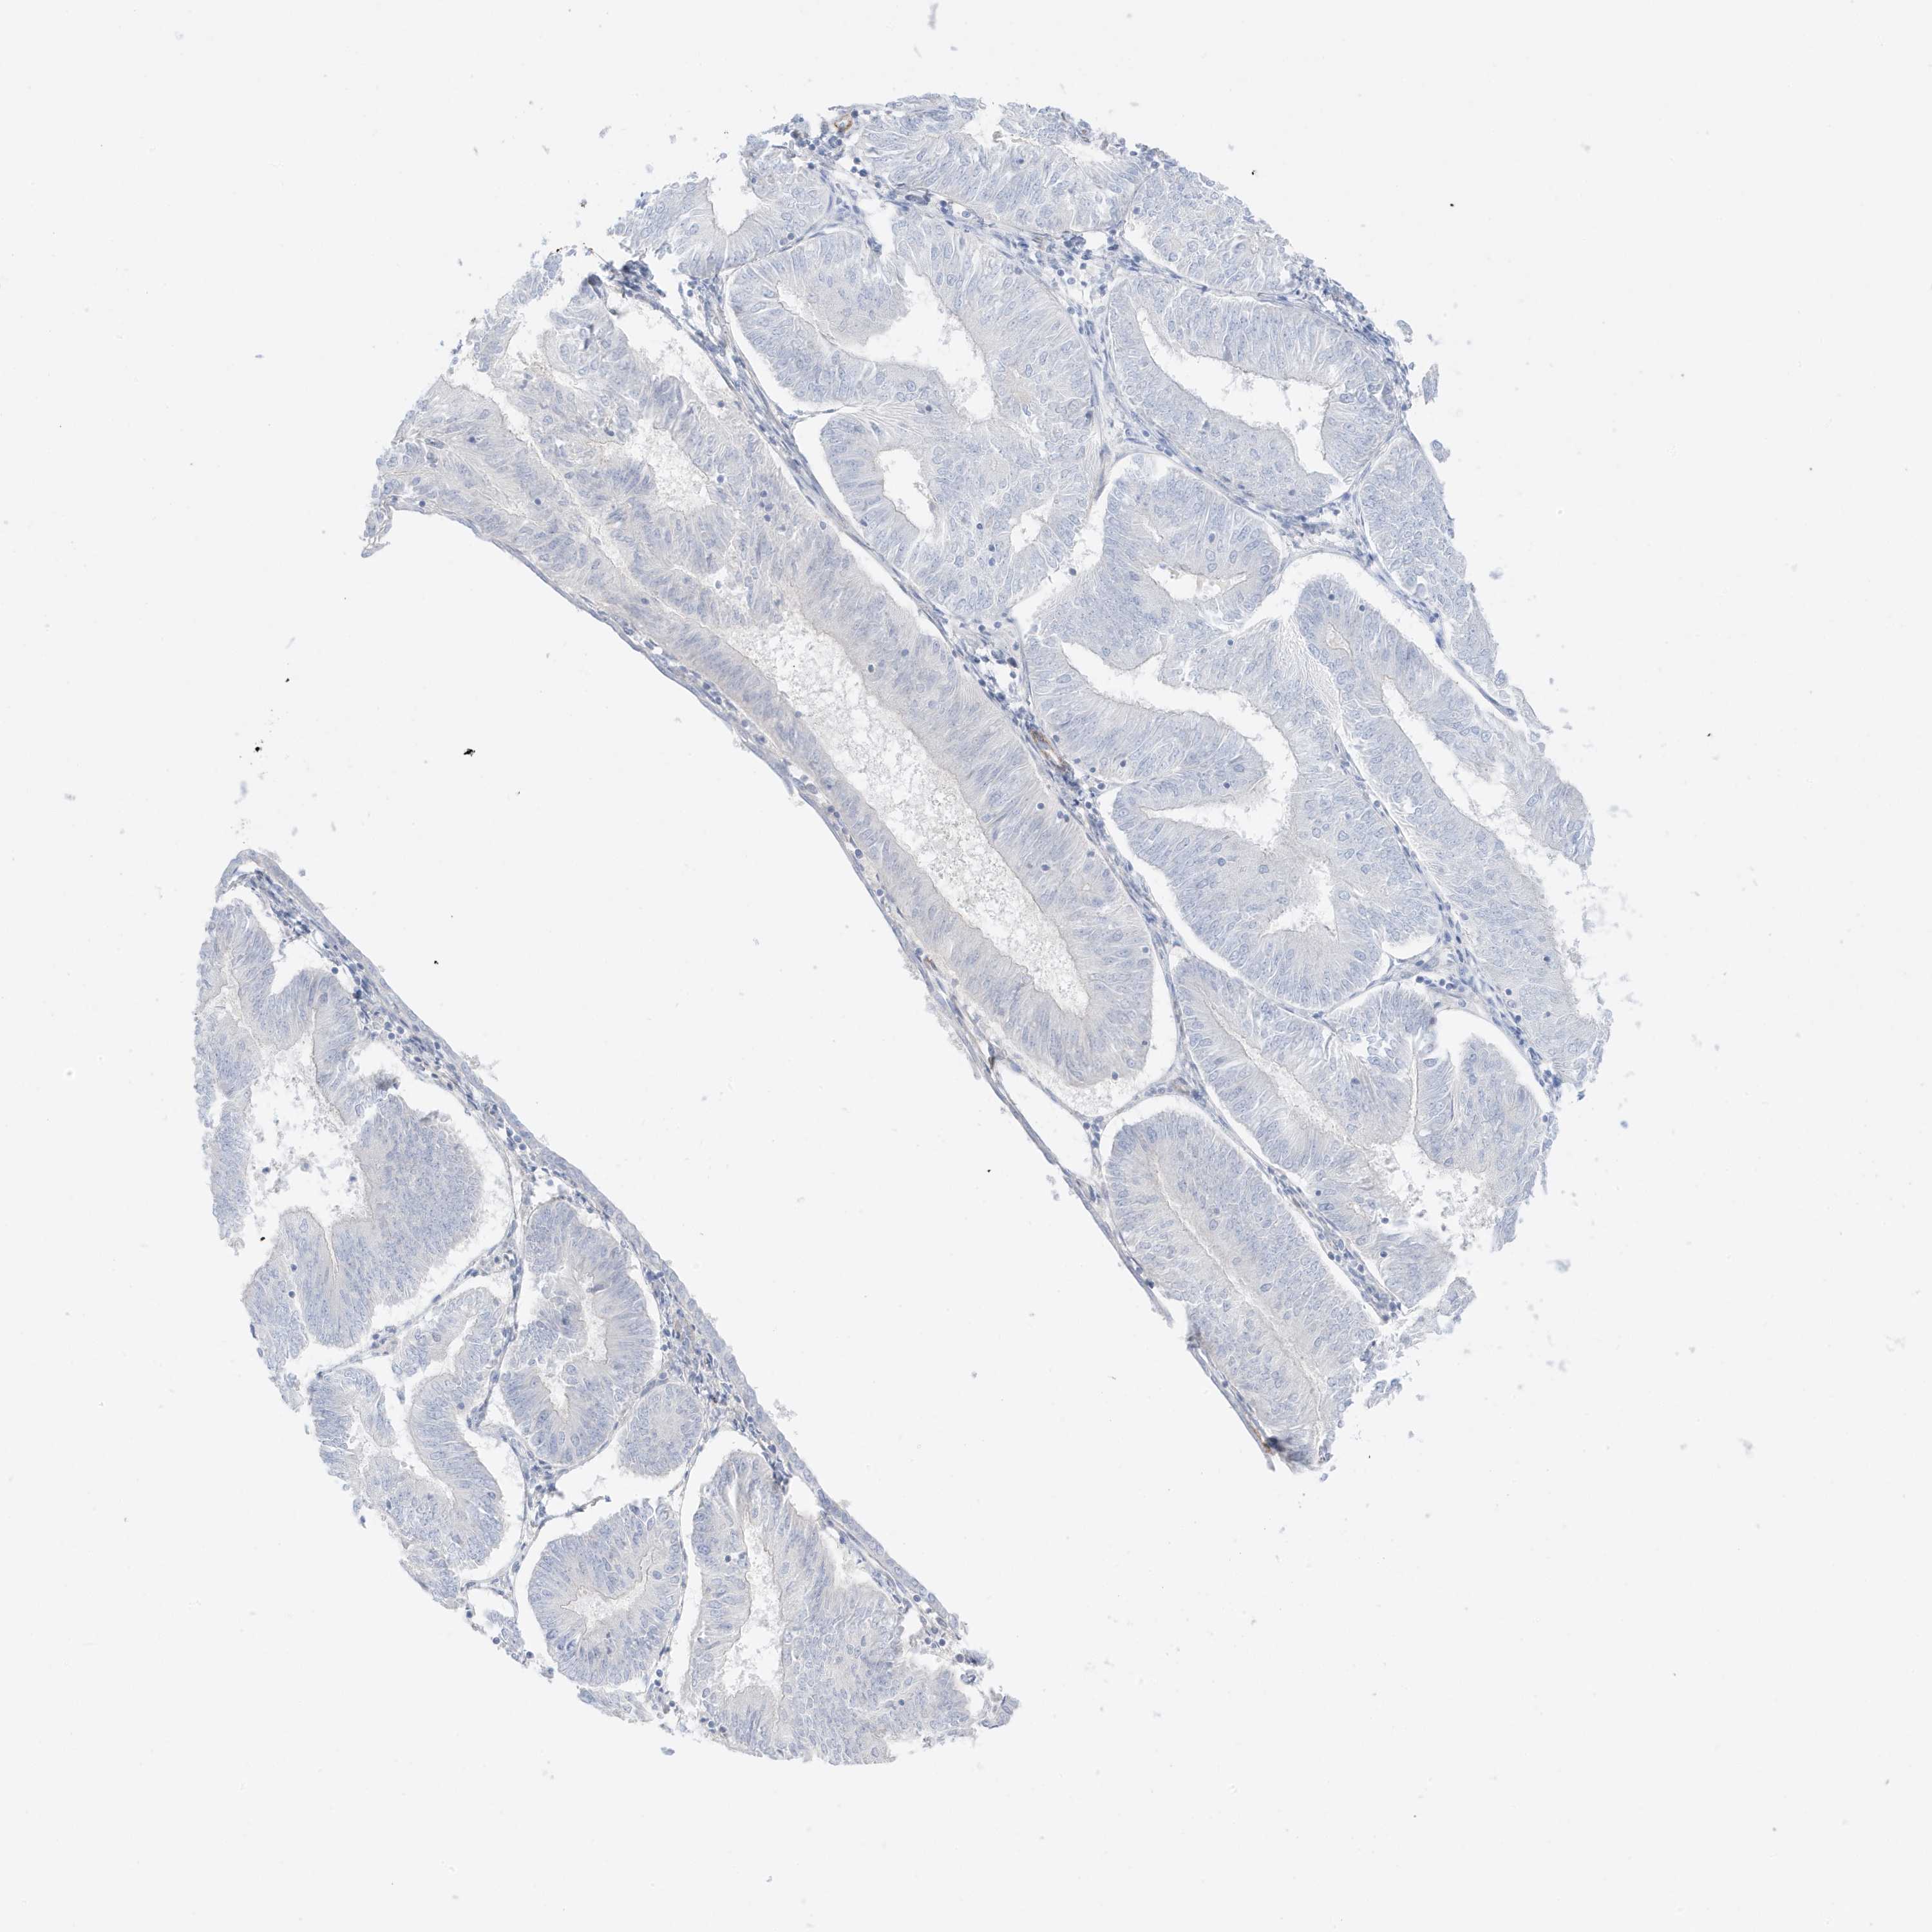

ENDOMETRIAL CANCER - Protein expressioni

A mouse-over function shows sample information and annotation data. Click on an image to view it in a full screen mode. Samples can be filtered based on level of antibody staining by selecting one or several of the following categories: high, medium, low and not detected. The assay and annotation is described here.

Note that samples used for immunohistochemistry by the Human Protein Atlas do not correspond to samples in the TCGA dataset.

Antibody stainingi

Antibody staining in the annotated cell types in the current human tissue is reported as not detected, low, medium, or high, based on conventional immunohistochemistry profiling in selected tissues. This score is based on the combination of the staining intensity and fraction of stained cells.

Each image is clickable and will lead to virtual microscopy that enables deeper exploration of all samples and also displays staining intensity scores, fraction scores and subcellular localization as well as patient and tissue information for each sample.

Antibody HPA035603

Antibody HPA035962

Staining

High

Medium

Low

Not detected

Intensity

Strong

Moderate

Weak

Negative

Quantity

>75%

75%-25%

<25%

None

Location

Nuclear

Cytoplasmic/membranous

Cytoplasmic/membranous,nuclear

Adenocarcinoma, NOS

Adenocarcinoma, metastatic, NOS